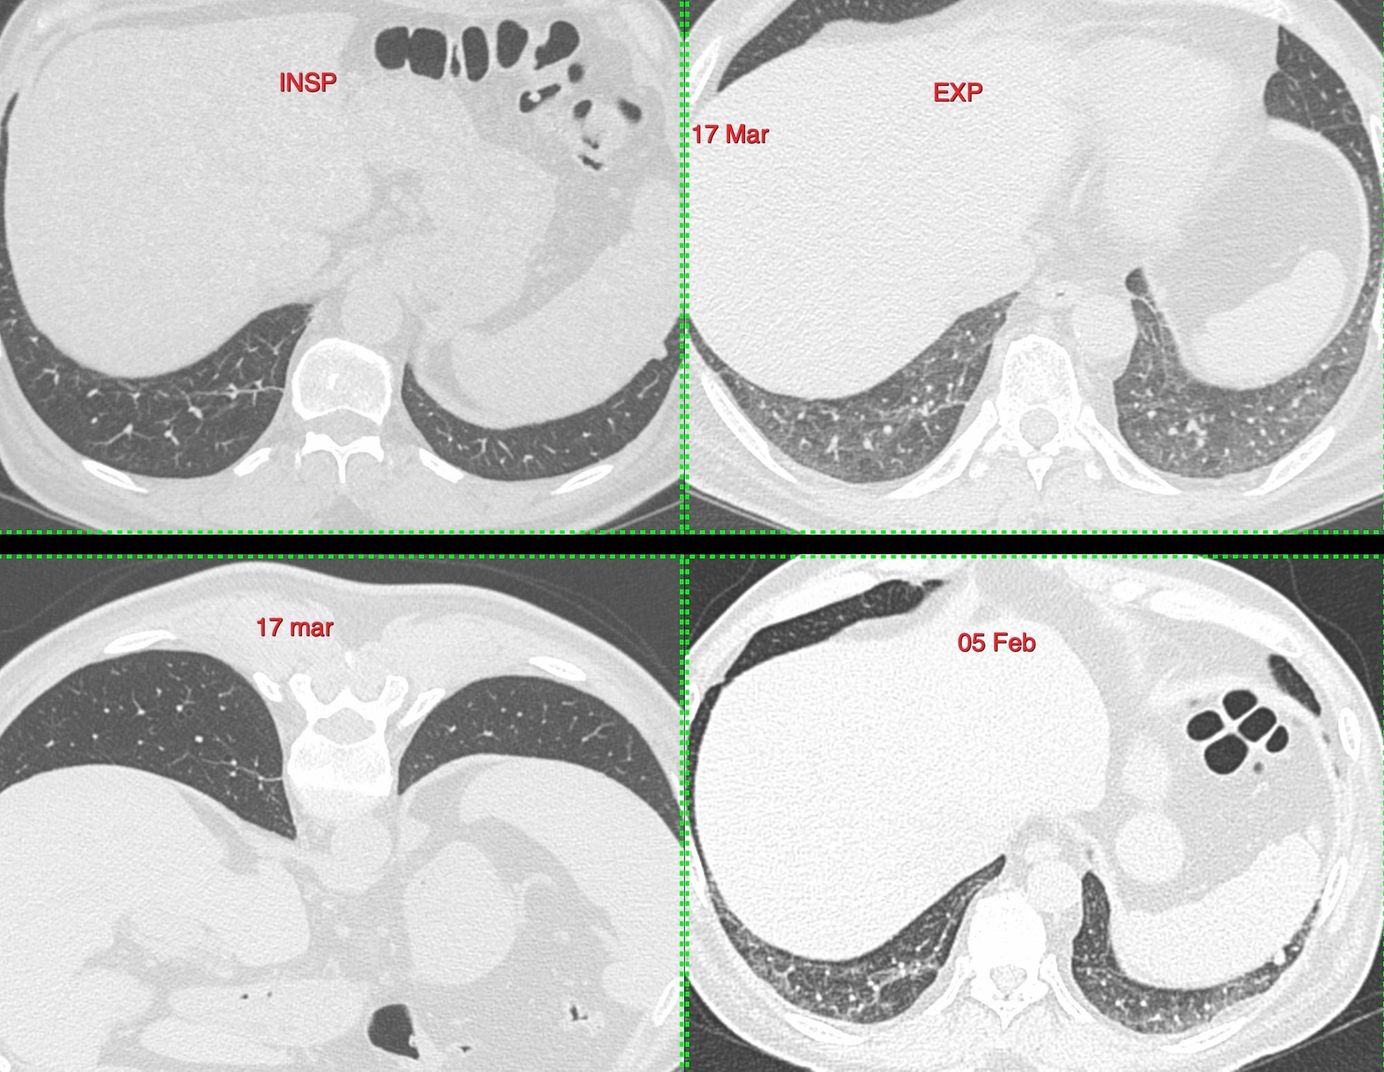

Case 11: The Tragi-Comic Consequences of a Poor Quality Scan Members Public

62-years old man diagnosed to have Covid-19 on an expiratory scan CT scan and the consequences thereafter. It is necessary to have a supine inspiratory scan at the least in all patients if expiratory and prone are not possible.

Bhavin Jankharia

Scan Protocol